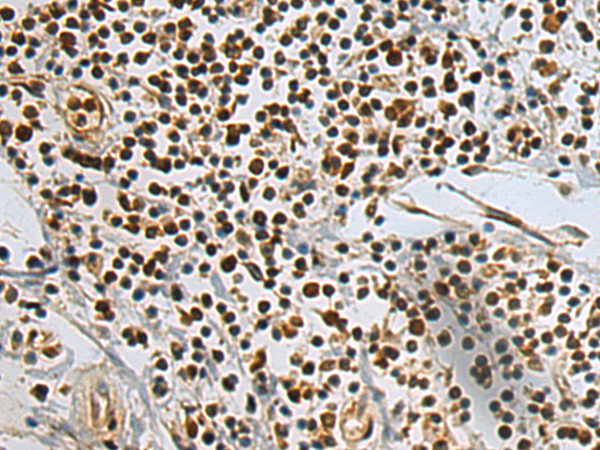

分类: 科研抗体货号: P10076别名: CRCS1; GalNAc-T12应用: IHC反应种属: Human, Mouse